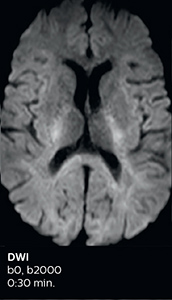

Improved diffusion imaging in stroke patients

Using MultiBand SENSE allowed the staff to improve their diffusion quality. “Our diffusion sequence was already fast before, about 40 seconds. Now with Elition, it still lasts 40 seconds, but we improved the spatial resolution by 0.2 mm and use high b-values to be more sensitive to visualize changes related to acute stroke,” says Dr. Savatovsky.

Acute right motor deficit and aphasia

In this patient with acute right motor deficit and aphasia, the b2000 diffusion weighted image is normal. The SWIp image demonstrates more prominent veins in the right hemisphere, which could reflect increased deoxyhemoglobin contents. Fast ASL shows low CBF regions in the left frontal lobe. A follow-up ASL after one hour demonstrates high CBF values in the same area. The final diagnosis was migraine with aura.

Acute right motor deficit and aphasia A

Acute right motor deficit and aphasia B